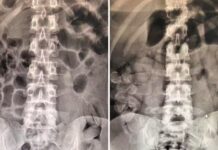

Raio-X mostra cápsulas de cocaína no estômago de quatro bolivianos em Araçatuba

Três mulheres e um homem, que relataram terem ingerido até 50 cápsulas da droga, são monitorados na Santa Casa.

Quatro passageiros de nacionalidade boliviana foram...